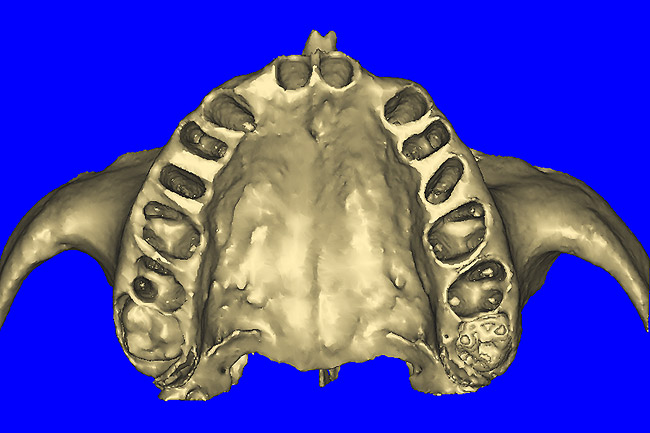

After the basic plan had been established, it was re-evaluated using interactive 3D images. The reconstructed 3D view of the maxilla clearly illustrated the extent of the bilateral facial concavities, and the root eminences of the adjacent and posterior teeth (Figure 7A). The placement of the virtual implants then was evaluated to ensure that the facial cortical plate was not perforated (Figure 7B). The implants were labeled individually as “7” and “10,” with the simulated yellow abutment projection indicating the facial-lingual inclination through the bone to the level above the incisal edge of adjacent teeth. The ability to gain a better understanding of these individual root forms can not be underestimated. The dental literature has suggested certain parameters for placing implants near teeth and implants next to other implants. However, there is little scientific 3D documentation to support these suggested rules.5-10 The use of an interactive treatment-planning software application permits closer scrutiny of previously difficult-to-visualize areas, and can now be used to redefine perceptions of spatial positioning of implants, especially when in close proximity to natural tooth roots, vital anatomy, and adjacent implants.27-29

Figure 7a  The 3D reconstruction showed (A) the facial concavities and root eminences, and allowed (B) for evaluation of virtual implant placement to ensure the facial cortical plate was not perforated.

Figure 7a

Figure 7b  The 3D reconstruction showed (A) the facial concavities and root eminences, and allowed (B) for evaluation of virtual implant placement to ensure the facial cortical plate was not perforated.

Figure 7b

Figure 14a  The information gained from (A) the 3D model was confirmed when (B) the flaps were elevated.

Figure 14a